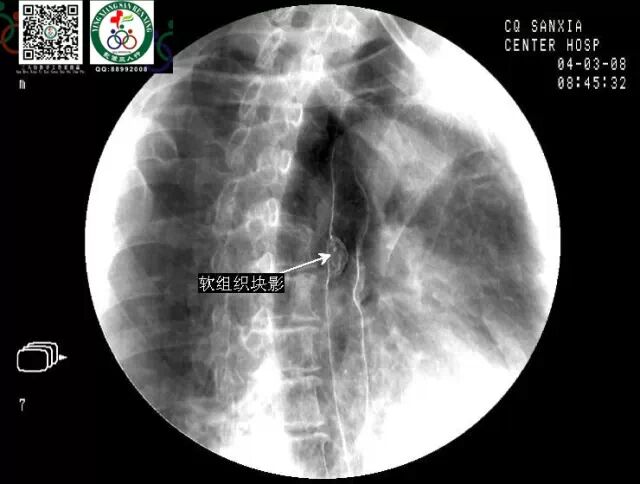

上消化道钡餐(同一病人,几个病典型征象有出现啦)